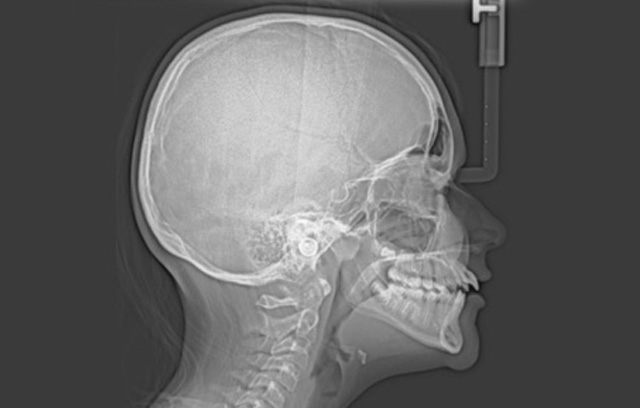

Specialized radiographs

All of our patient pictures and x-rays are digital, which facilitates analysis and sharing of copies with you or other dentists and specialists involved in your treatment. Furthermore, we are equipped with a new Cone Beam 3-Dimensional x-ray machine, which allows us a clearer view when needed for better treatment planning.